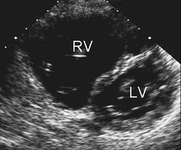

Imagem de ecocardiografia do eixo paraesternal curto revelando um aumento ventricular direito em um paciente com defeito do septo atrial (DSA). (VD) ventrículo direito; (VE) ventrículo esquerdo

Imagem cedida por Patrick W. O'Leary, MD

Imagem de ecocardiografia apical de 4 câmaras revelando dilatação do ventrículo direito em um paciente com defeito do septo atrial (DSA). (AD) átrio direito; (VD) ventrículo direito; (VE) ventrículo esquerdo